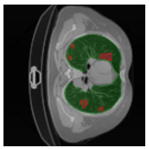

In Table 6, a comparison of the ground truth and prediction results of each model is presented in 2D, along with the 3D projection of each model. The visual analysis of the predictions provides additional insights into the performance of each model. The visualizations demonstrate that Attention UNet captures the intricate details of the lung construction more accurately, resulting in more precise segmentation of the infected areas compared to other models.

Table 6.

Comparison of ground truth and model prediction results using UNet, LinkNet, Attention UNet, UNet 3+, and TransUNet.